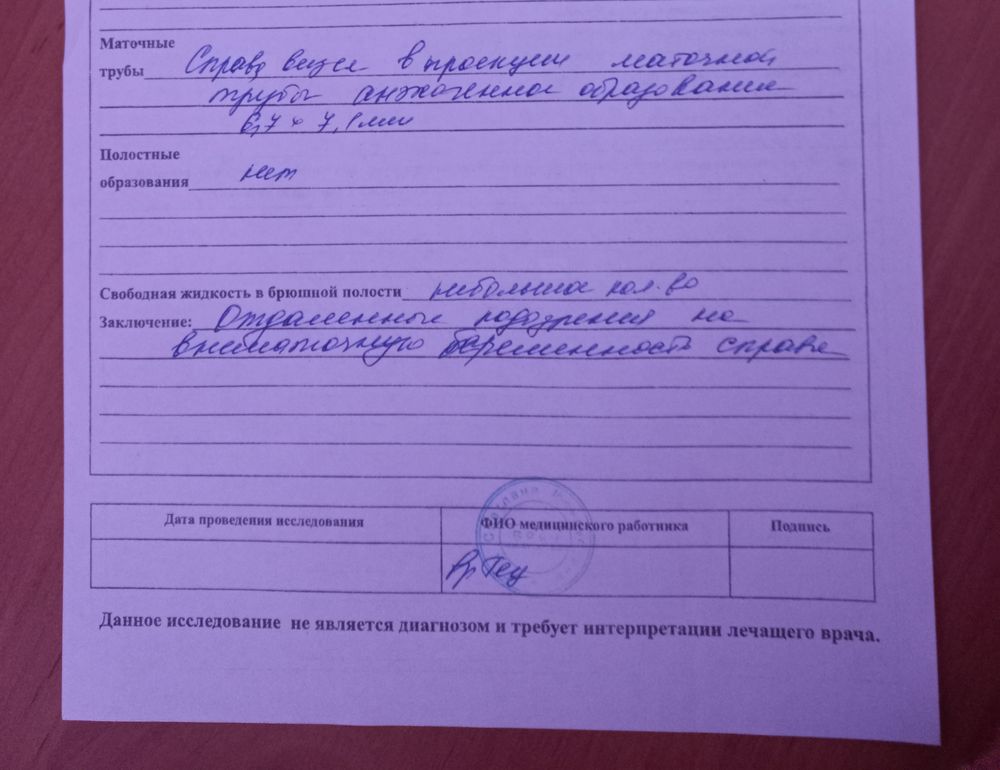

Не менее интересно что же это все таки за эхогенное образование в трубе, если по ХГЧ беременности нет.

Снимок узи прикрепила. Может быть я чего то не понимаю уже от постоянного чувства тревоги и переживания ВБ или нет. Как то не особо на операционный стол ложиться.

Настасья, может это гидросальпинкс?

Настасья, образование жидкости в трубе

Может, это гидросальпинкс? При нем тоже может быть задержка.